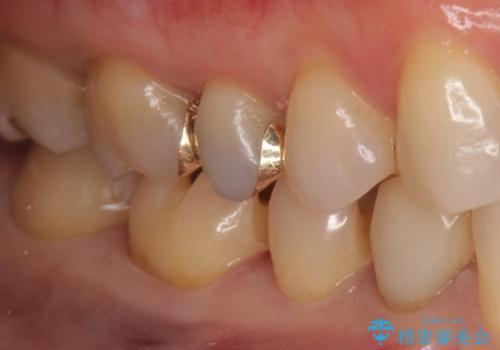

下の歯の銀歯が目立つ

- 口を開けた時、銀の詰め物が目立つとのことで来院。

拡大鏡下で詰め物を外し、う蝕がない事を確認して、セラミック(e-maxインレー)で治療を行いました。